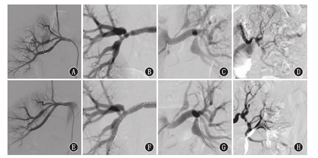

所有患儿均为FMD引起的单侧肾脏分支病变,无其他脏器动脉受累。涉及二级分支6例,涉及三级分支2例;累及2条及以上分支动脉4例,累及1条分支动脉4例;伴有囊性扩张或动脉瘤5例,其中发生夹层动脉瘤伴局部肾梗死患者1例,伴动脉瘤且动脉瘤位于分支分叉处者1例;仅发生动脉狭窄3例。局灶性病变者5例,其中管样狭窄2例;多灶性病变(指呈"串珠样"改变或多处血管损害)3例。相关病变类型分布见表1,图1、图2。

Different imaging findings of renal fibromuscular dysplasia in child with branch arterial disease before and after operation

注:A、B、C、D:术前病变特点;E、F、G、H:术后造影表现

A,B,C,D:preoperative lesions characteristics;E,F,G,H:postoperative angiography

FMD主要发生于幼年或青年、中年女性,根据病变主要累及动脉壁的层次,FMD常分为3个组织学分型:内膜纤维组织增生型、外膜纤维组织增生型、中膜发育不良型,最常见为中膜发育不良型,表现为典型的"串珠样"改变或肾动脉中段和远端的多灶性狭窄,其他2种类型主要表现为管样狭窄或局灶性病变[7,8]。本研究报道的8例患儿表现为不同的分支病变类型,包括"串珠样"改变,局灶性狭窄,长段管样狭窄,或合并动脉瘤,或合并夹层表现,比较全面地显示了FMD引起分支病变特点。